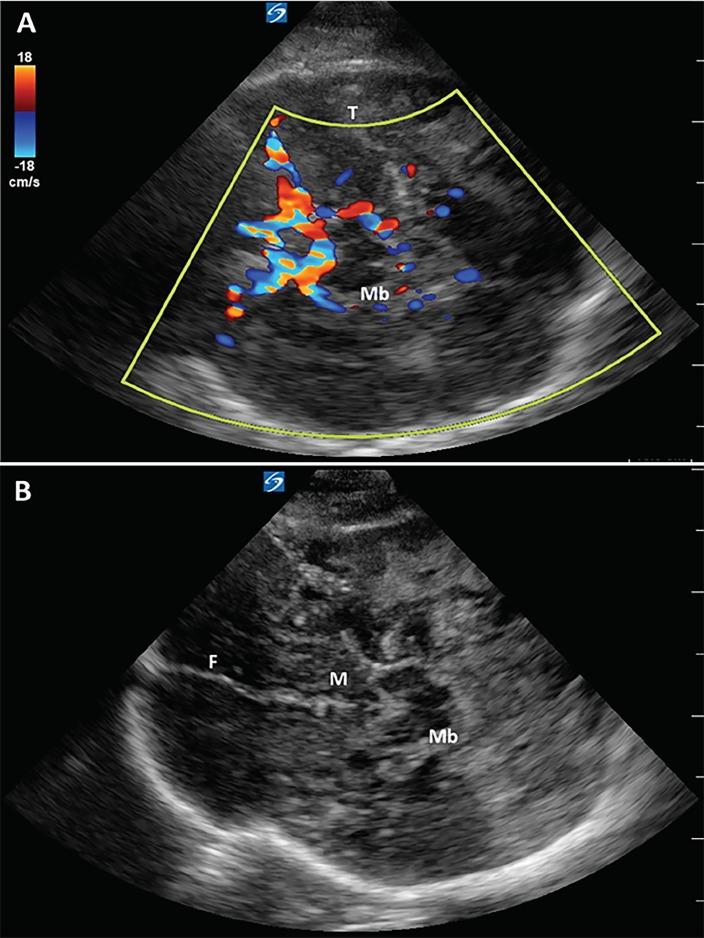

Point-of-care Cranial Ultrasound in a Hemicraniectomy Patient.

Clin Pract Cases Emerg Med. 2018 Sep 10;2(4):375-377. doi: 10.5811/cpcem.2018.7.39379. eCollection 2018 Nov.